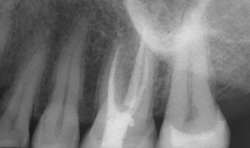

Canal measurement (m1) – The memory one mode (Fig. 6) allows for the electronic measurement of the root canal. The motor doesn’t rotate in this mode. With a lip clip applied to the corner of the mouth and file holder attached to the file in the root canal, the length can be determined (Fig. 7). As the file approaches the minor diameter or apical constriction, there’s an audible sound and the file position and overall length can be confirmed on the LCD display.

Fig. 7